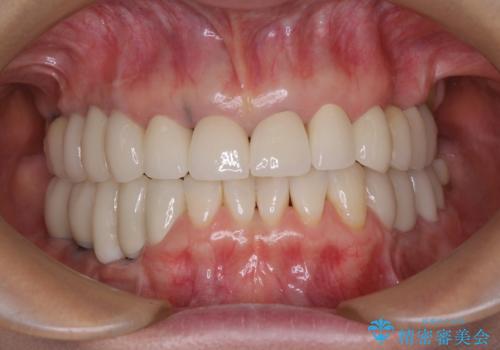

- 以前治療した歯が欠けたり、痛みを感じたりしているとのことで来院された患者様です。

アメリカ国内を転々としながら治療を行ったため治療跡がモザイク様で、クラウンが壊れていたり、抜歯が必要であったりしていました。

上下左右すべての奥歯に処置が必要であり、同時に行うと食事が取りにくくなってしまったり、手前の歯に負担がかかって初診時よりも状況が悪化したりする可能性があるため、片方ずつ処置を進めて行くこととしました。

下顎右側は骨造成を併用してインプラント治療を行い、その他の奥歯もインプラントや歯周外科処置を併用して補綴治療を進め、最後に前歯部の欠けてしまったセラミッククラウンを作り替えることとしました。